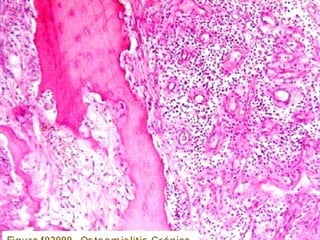

Imagen microscópica de osteitis, inicialmente existe una etapa de

osteoclastosis seguida por regeneración. No siempre el hueso

regenera en su totalidad y sigue el curso de cualquier inflamación

dejando un area de tejido fibroso que con el tiempo puede

calcificarse (hueso denso)

Manejo con antibióticos obligado

Revisión periódica